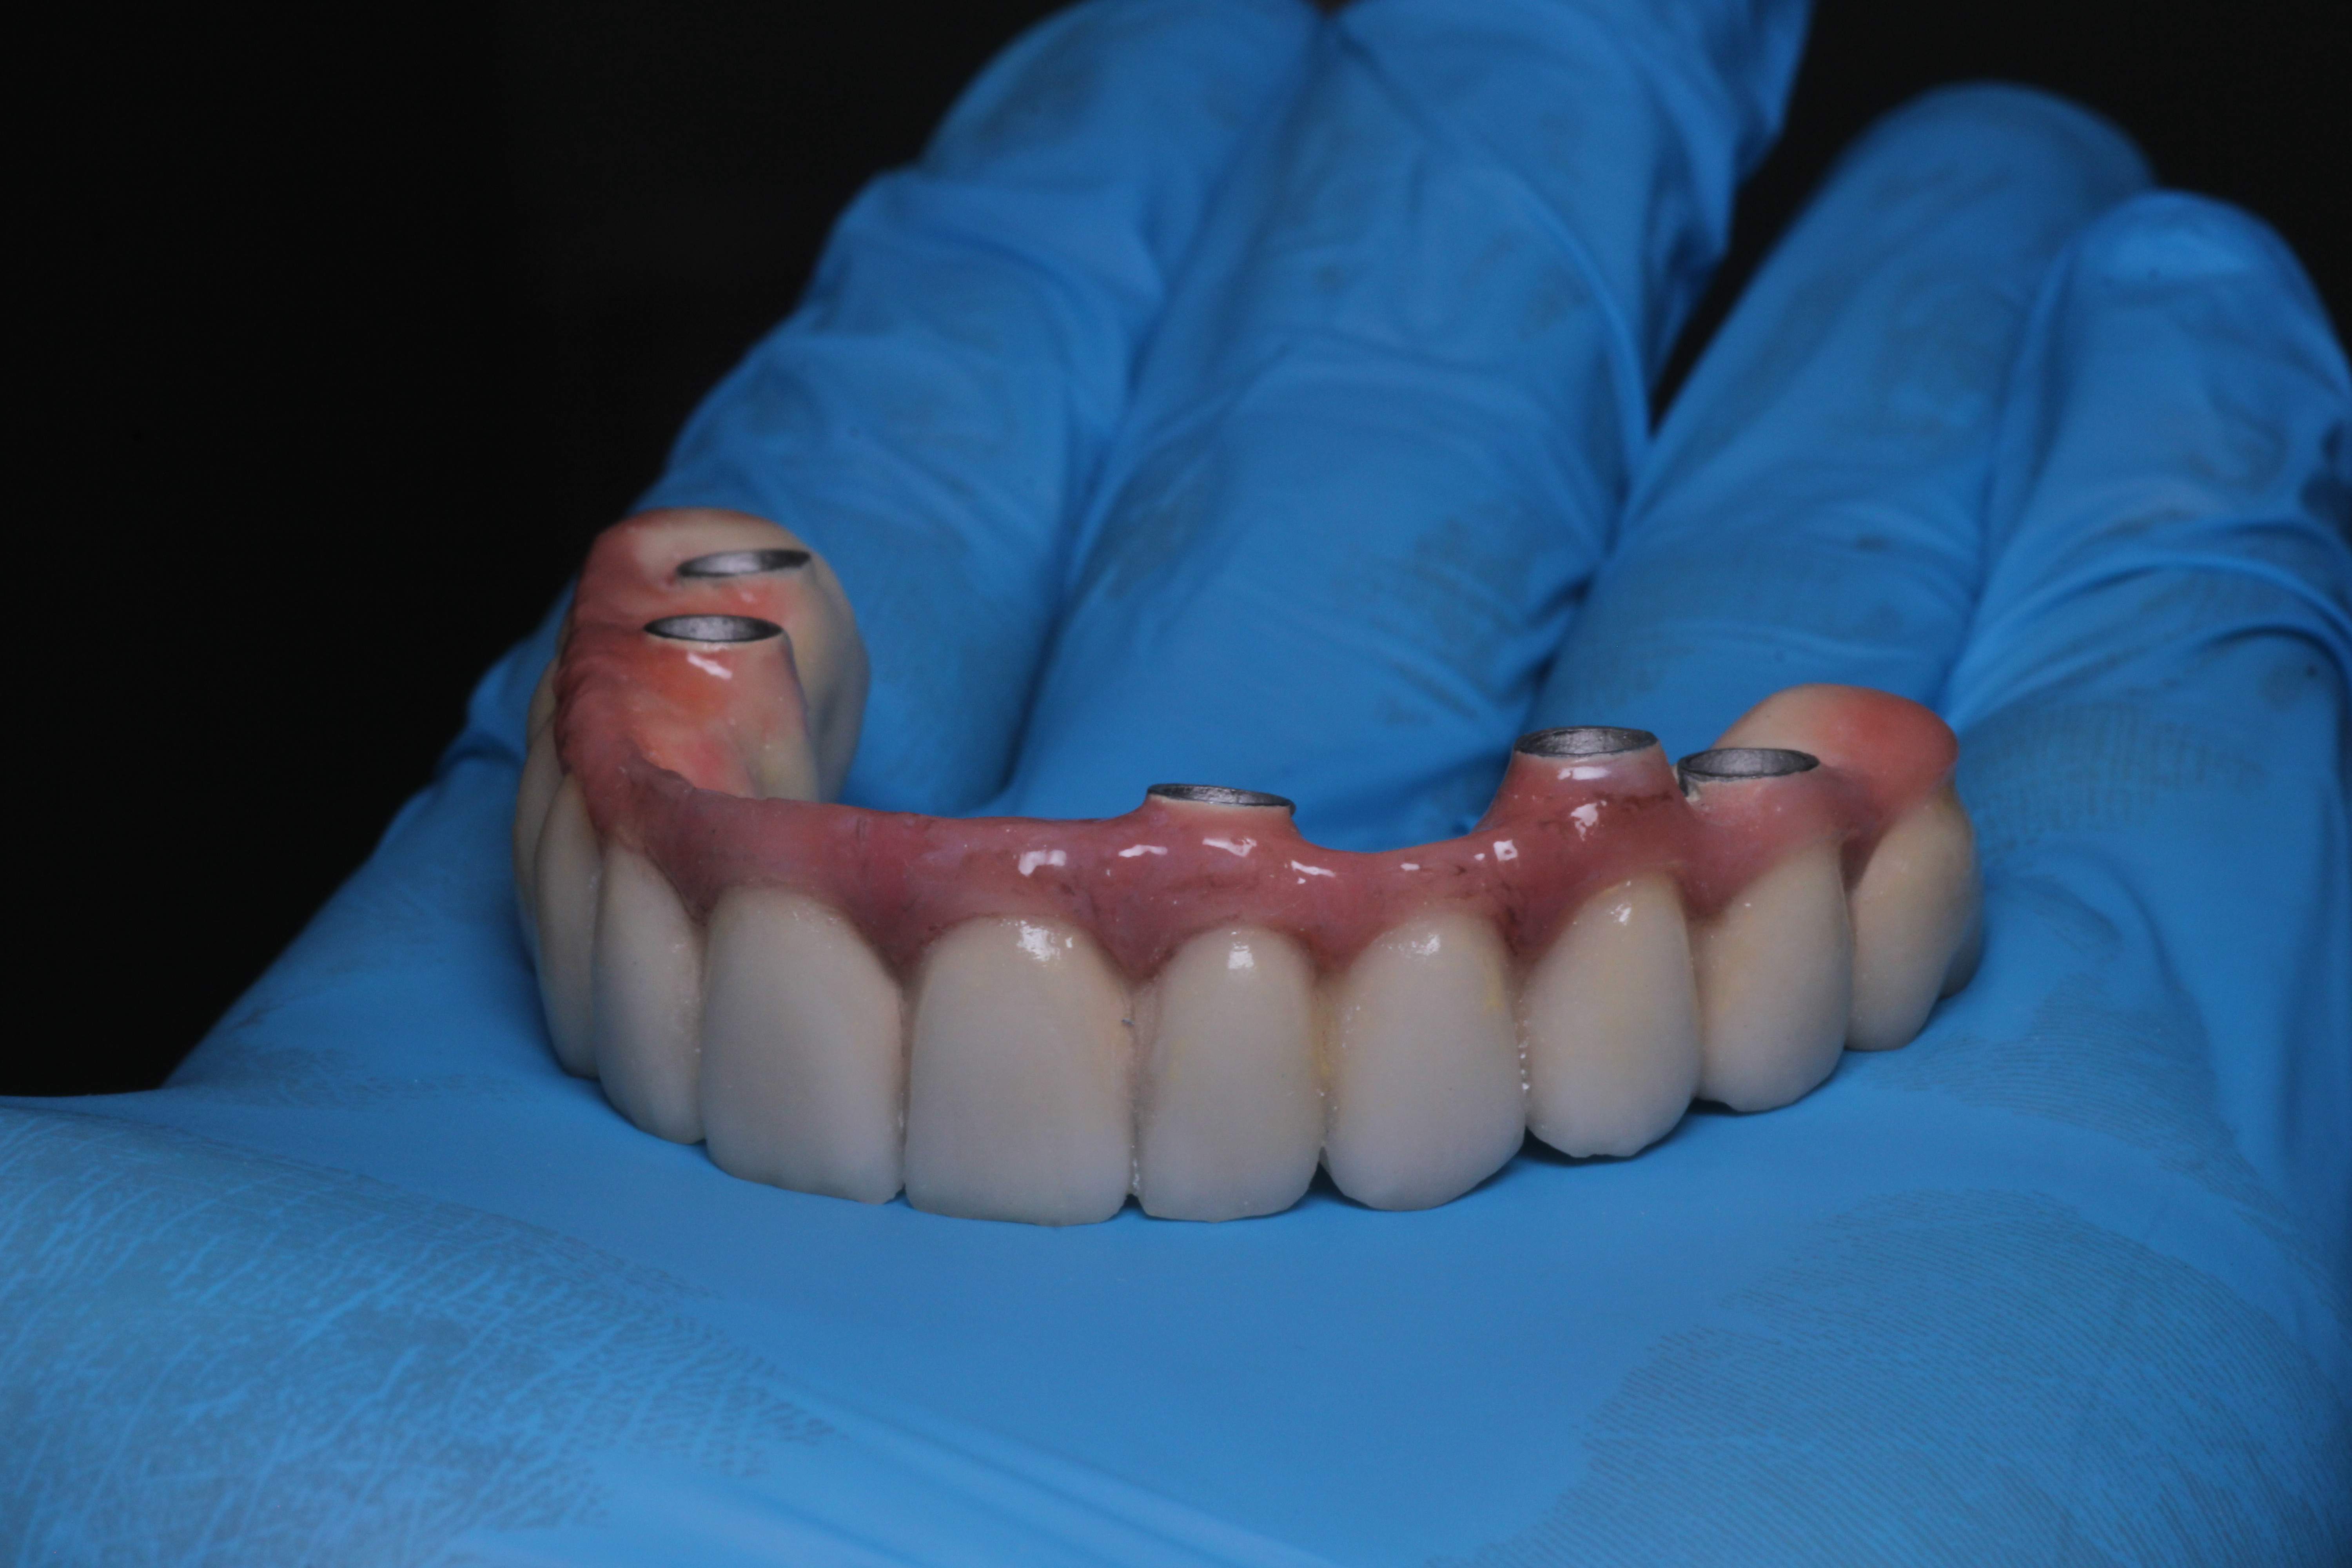

Prótesis fija diseñada con encía artificial de alta estética y naturalidad.

Verificación minuciosa de la prótesis antes de su instalación definitiva.